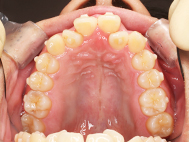

After

装着が目立ちたくないとの事でアライナ-での矯正を希望されました、歯の間を削り少し歯の幅をスリムにして綺麗なアーチに並びました。